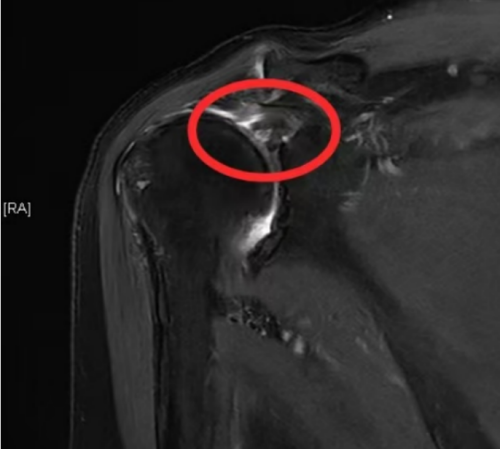

运动医学科就诊。科室主任李良军接诊后,经过详细的体格检查及核磁共振检查,诊断张奶奶为右侧巨大肩袖撕裂,并伴有肩峰撞击,建议住院接受手术治疗。

核磁检查发现右肩肩袖损伤